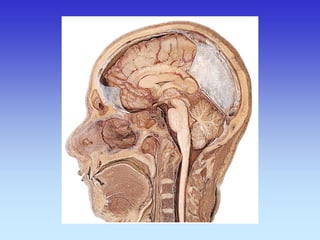

Sagitalni presjek

Koronarni presjek